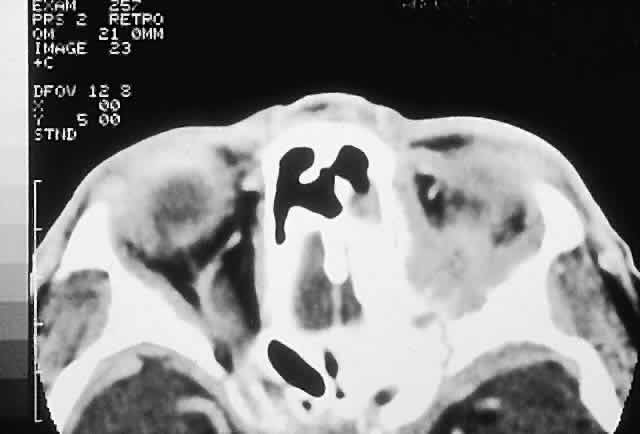

MYELOMA. Multiple myeloma and more rarely solitary plasmacytoma may involve orbital bone.140–143 These tumors affect those older than 50 years and present with a subacute onset of pain and proptosis. In the case of multiple myeloma, there are usually systemic manifestations such as bone pain, fever, and fatigue, as well as urinary and serum protein abnormalities. Radiologically, an osteolytic area with a contiguous soft tissue mass is the rule. Histologically, the tumors are composed of broad sheets of malignant plasma cells varying in appearance from mature to blastlike.40

LANGERHANS CELL HISTIOCYTOSIS. Langerhans cell histiocytosis consists of a variety of syndromes resulting from the proliferation of Langerhans cells. Localized bone involvement (eosinophilic granuloma) is prevalent in boys ages 3 to 10 years. These children characteristically develop proptosis as a result of focal lytic superolateral lesions associated with soft tissue expansion.144–146 We have seen six cases of localized Langerhans cell histiocytosis, and each demonstrated a characteristic CT appearance of a central radiolucent area with an enhancing rim (Fig. 12). Histologically, there is a granulomatous and histiocytic infiltrate with Langerhans cells and prominent eosinophils.147 Localized periorbital disease is responsive to curettage, intralesional steroid injections, or low-dose radiation therapy. The prognosis is poorer in younger patients with visceral involvement.

Fig. 12. This 9-year-old boy had a 3-week history of right progressive proptosis associated with inward and downward displacement of the globe. CT demonstrated an osteolytic mass with an enhancing rim destroying the lateral orbital wall. Biopsy revealed Langerhans cell histiocytosis, and he was treated with surgical excision and intralesional steroids. He remains well after 5 years of follow-up. (Rootman J, Stewart BA, Goldberg RA: Orbital Surgery: A Conceptual Approach, p 45. Philadelphia: Lippincott-Raven, 1995.)